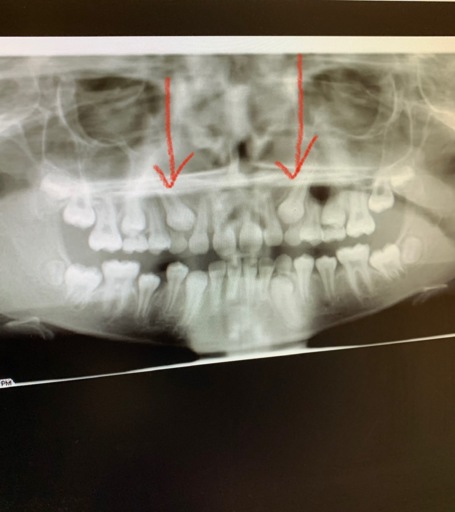

I have a very large cavity on one of my upper molars that caused severe pain for several weeks and went up through my sinuses. I live below the poverty level and have no insurance, but I headed to the ER because it was radiating out farther. I was put on penicillin and referred to our local, county health department where the only adult dental care offered is extraction. They have no anesthesia but did have Novocaine. He did an x-ray and said the roots were very deep but I know I don't have the option for a filling or root canal so I said that was fine. The Novocaine deadened every area of my mouth except the one nerve right in my tooth. I told him several times I was feeling pain, not pressure. After an hour of him attempting to extract the tooth, I had to have him stop because my whole body was shaking and I was sobbing no matter how much I tried to stop. I asked what now and there were no suggestions but he did inform me the tooth was still very firmly in my mouth and would not fall out on its own. For several days afterward, I had quite a bit of pain at the site of the injections (he injected in multiple locations 3 separate times)and the pain I had gone in with, though the radiating pain had stopped after completion of the penicillin. This was a month ago. I brush regularly and only use one side of my mouth to eat with because contact between the upper and lower teeth is very painful on the right side. This week, I have had some more aching but I figured I was just grinding my teeth again (yes, I have apnea and a bi-pap) but yesterday, the pain in the gum surrounding the tooth and roof of my mouth in the area where the dentist had done the injections returned as if he had been yanking on my tooth again. He did damage the tooth quite a bit during the attempted extraction with the ...pliers (not sure of the correct term) because I don't think he thought the tooth would be remaining. I am at a loss what to do now because I am already eating soft foods and the pain is bad enough, it woke me from sleep. I am taking an OTC NSAID, rinsing with salt water, and avoiding sugary or acidic foods. What else can I do?